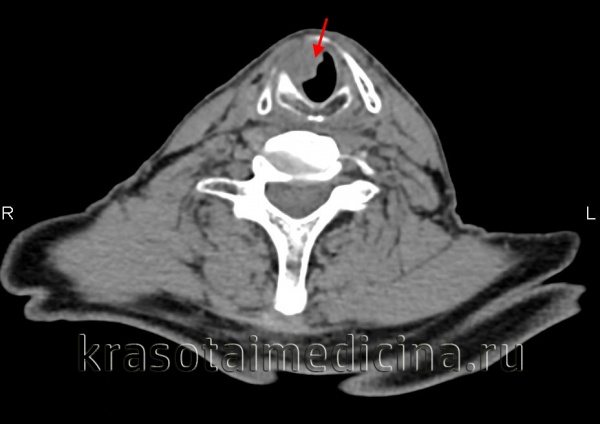

(Справа) При аксиальной КТ с КУ определяются аналогичные изменения: инвазия окологортанной жировой ткани с обеих сторон и левой черпалонадгортанной складки. Опухоль выбухает через вырезку щитовидного хряща. Грушевидный синус не изменен. (Слева) При аксиальной КТ с КУ визуализируется небольшое объемное образование в надгортаннике с признаками инвазии предгортанного пространства (стадия Т3). Опухоль симметрична, что затрудняет ее выявление, тем не менее, надгортанник никогда не должен выглядеть настолько утолщенным или накапливать контраст, как здесь. Лимфоузлы этом случае не определяются (их следует искать с обеих сторон, особенно при опухолях надгортанника.